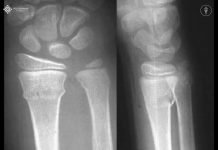

Röntgen -X-Ray

Kırıkların tanısında ve tedavi planlamasında olmazsa olmazımız radyolojik incelemedir. Kırıldığı düşünülen tüm uzun kemiklerin röntgenleri, var olan yaralanmayı değerlendirmek amacıyla kırık bölgenin yakın ve uzak eklem kısımlarını da içererek çekilmelidir. Yani kemiğin alt ve üst eklemlerinin de aynı filmde görülmesi gerekmektedir. Her kemiğin en az ön-arka ve yandan olmak üzere iki pozisyonda röntgeni çekilmelidir. Ayak bileği, ayak ve el kırığı şüphesinde oblik filmler çekilmelidir. Omuz eklemi, patella ve naviküler kemik gibi bölgelerin radyolojik incelemesinde özel pozisyonlarda röntgenler çekilmelidir. Şüpheli durumlarda veya daha detaylı radyolojik incelemenin gerektiği durumlarda BT, MR gibi ileri radyolojik inceleme yöntemlerinden faydalanılmalıdır.

TANI

Kırıkların tanısında ve tedavi planlamasında radyolojik incelemenin değeri büyüktür. Kırıldığı düşünülen kemiğin alt ve üst eklemlerinin de aynı filmde görülmesi gerekir. Her kemiğin en az ön-arka ve yandan olmak üzere iki pozisyonda röntgeni çekilmelidir. Ayak bileği, ayak ve el kırığı şüphesinde oblik filmler çekilmelidir. Omuz eklemi, patella ve naviküler kemik gibi

bölgelerin radyolojik incelemesinde özel pozisyonlarda röntgenler çekilmelidir. Şüpheli durumlarda veya daha detaylı radyolojik incelemenin gerektiği durumlarda BT, MR gibi ileri radyolojik inceleme yöntemlerinden faydalanılmalıdır.